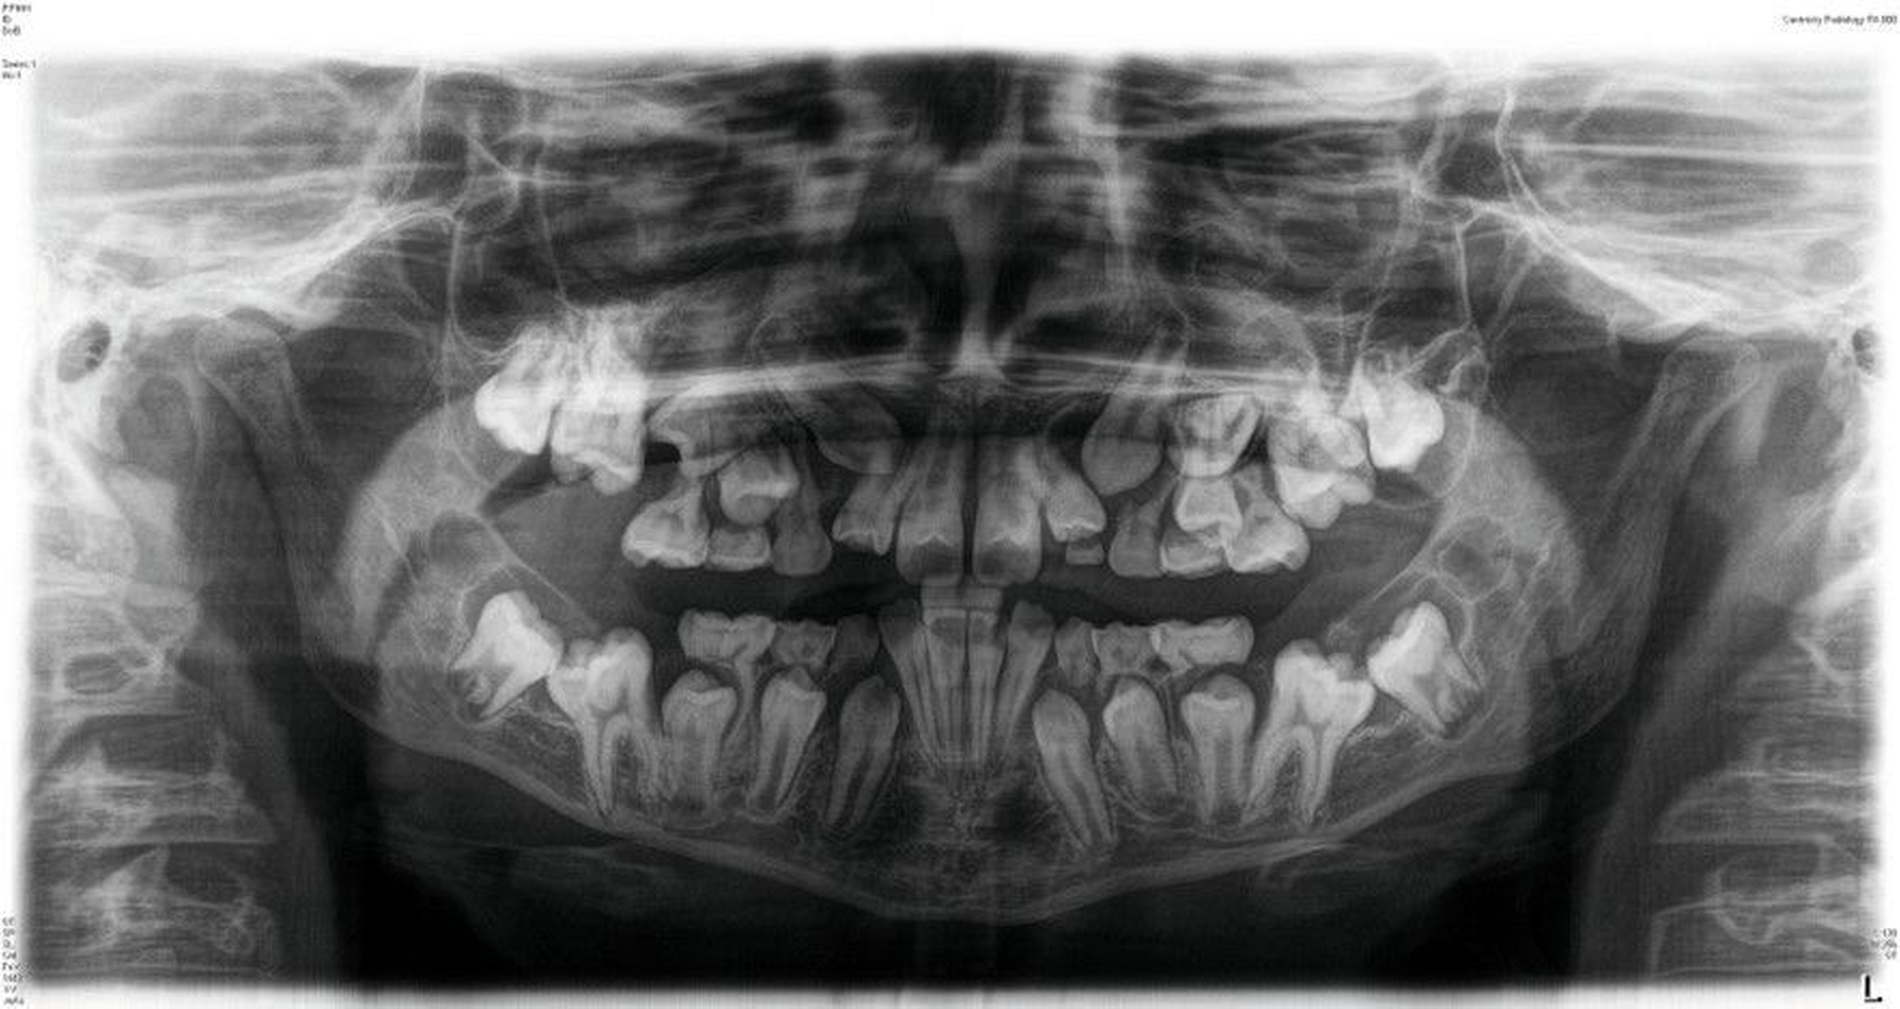

Ein zwölfjähriger Patient stellte sich in der Poliklinik für Kieferorthopädie des Universitätsklinikums Tübingen mit einer skelettalen Klasse-III-Konfiguration, einer Angle-Klasse III, einem Kreuzbiss auf der linken Seite und transversal schmalem Oberkiefer vor. Die Anamnese ergab ein vermindertes Hörvermögen, weshalb der Patient Hörgeräte trug. Darüber hinaus wurde keine Medikamenteneinnahme oder Allergie angegeben. Er wies mit einem dentalen Alter von sieben Jahren einen verzögerten Zahndurchbruch auf. Der initiale intraorale Befund zeigte die in situ befindlichen Zähne 11, 21 und 32–42. Die Zähne 12 und 22 eruptierten in Inklinationsfehlstellung. Die Milcheckzähne und -molaren befanden sich noch in situ. Die Sechsjahrmolaren waren nicht eruptiert und zeigten eine Verlagerungstendenz, insbesondere im Unterkiefer (Abbildung 1, Tabelle 1).

Die initiale Panoramaschichtaufnahme zeigte die Verlagerung mehrerer Zahnkeime sowie einen Platzmangel der Eckzähne und der Prämolaren im Oberkiefer (Abbildung 1b). Die Keimkrone von Zahn 13 wies dabei eine enge Lagebeziehung zum Zahnkeim 12 auf (Abbildung 1b). Die bereits eruptierten permanenten Frontzähne zeigten eine Angulations- und eine Inklinationsfehlstellung. Im distalen Bereich waren keine Durchbruchshindernisse erkennbar. Vor Beginn der kieferorthopädischen Behandlung wurde eine Primäre Zahndurchbruchsstörung (Primary Failure of Eruption – PFE) genetisch ausgeschlossen.